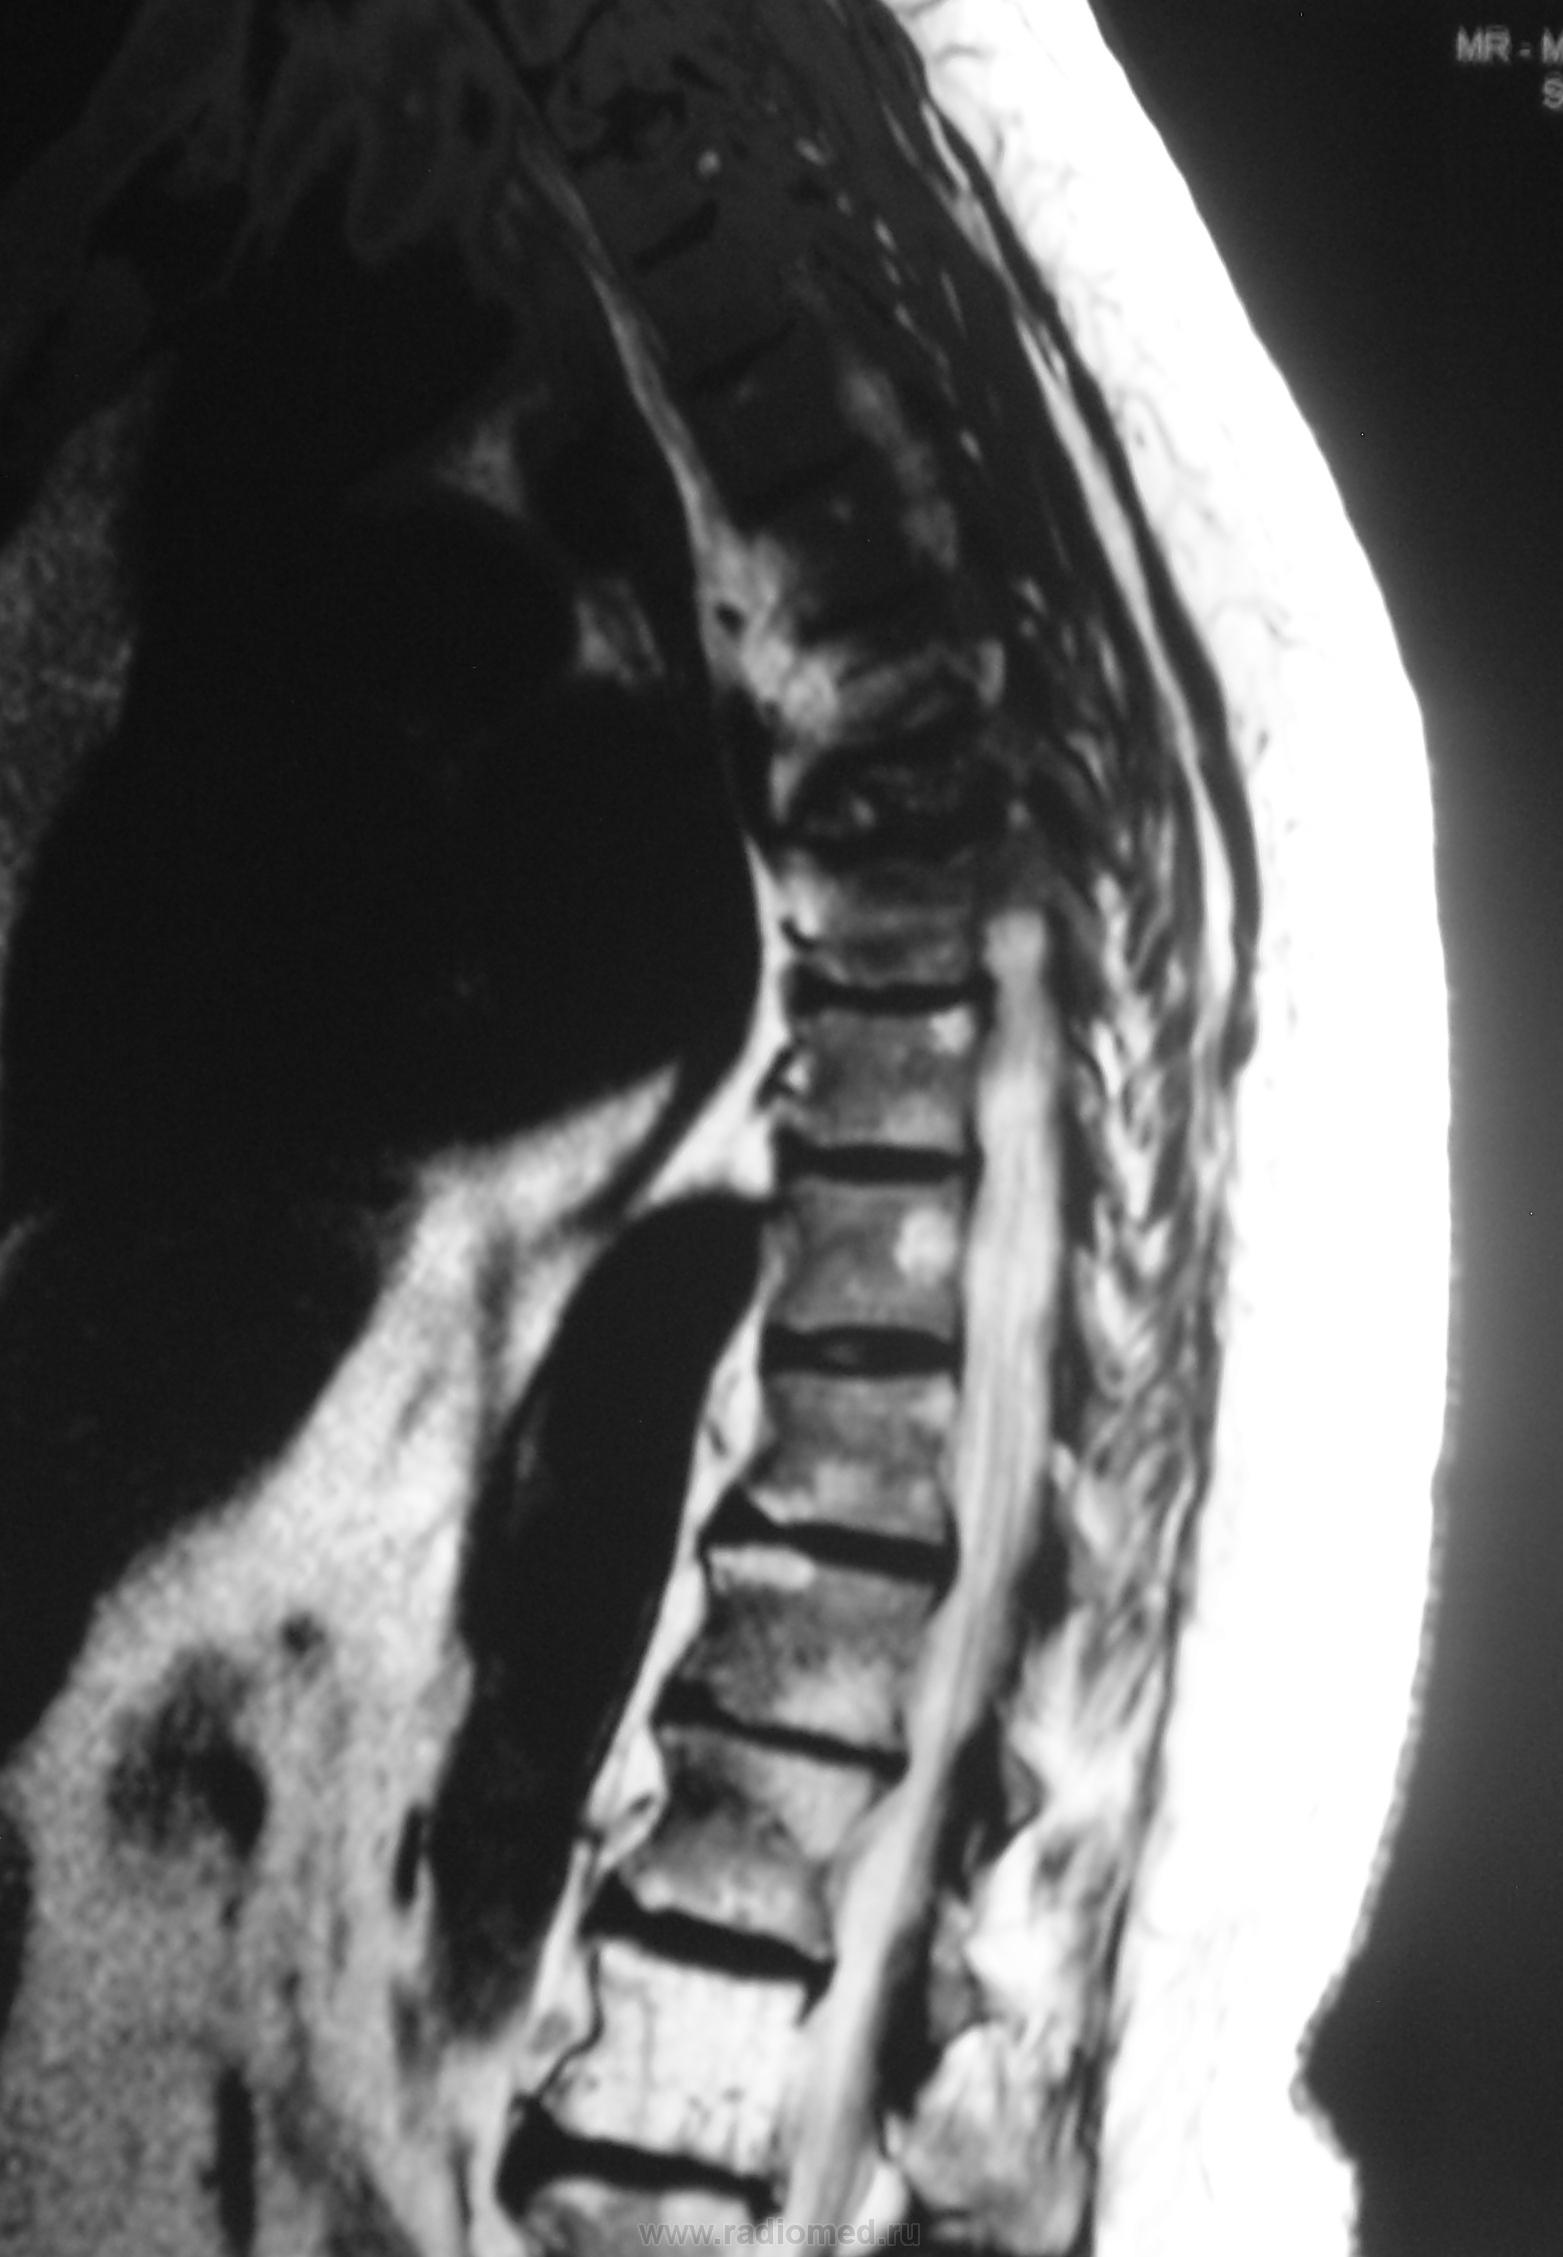

Пациентка - мама нашего коллеги. Жалобы на боли в позвоночнике.

На мой взгляд в верхнегрудном отделе наиболее выраженные изменения опухолевой природы, хотя и на других уровнях есть изменения. По отдельным слайдам не складывается полная картинка, аксиальных томограмм этого отдела нет совсем.

Не опровергая мнения Евгения Второго: а не выглядит ли то, что "не красиво" в верхнегрудном отдлеле как "артефакты"? Складывается впечатление, что "изменения" с тел позвонков переходит на средостение и на грудину... Картинка как бы в "градиенте"... По остальному позвоночнику - дегенеративные изменения + гемангиомы + последствия компрессионного перелома тела позвонка; возможно ошибаюсь... Нужно смотреть шейно-верхнегрудной...

Спондилит туберкулезный..

спондилит то есть, с компрессией тела позвонка и паравертебральными изменениями. и если вверху артефакты (граница каналов катушки, неправильное позиционирование или типа того) - тогда спондилит выходит на первый план. только насчёт туберкулёзного я бы не стал так уж уверенно. может просто опыта нет в дифдиагностике туберкулёзного и банального спондилитов (у меня).

Компрессионный перелом позвонка, вокруг изменения мягких тканей, похожие на натечник. Хотя рассмотреть бы это в нормальном качестве... DICOMа нету?

Я не занимаюсь сам, этими прекрасными высокими технологиями. После исследования, проведенного в области были выставлены множественные гемангиомы. Боли в позвоночнике у пациентки были и ранее, но в определенный момент резко усилились, по всей видимости, тогда и произошла "компрессия". Мне не верится, что это гемангиомы. Я более склонялся к специфике (туб спондилиту), но это мнение во многом больше интуитивно.